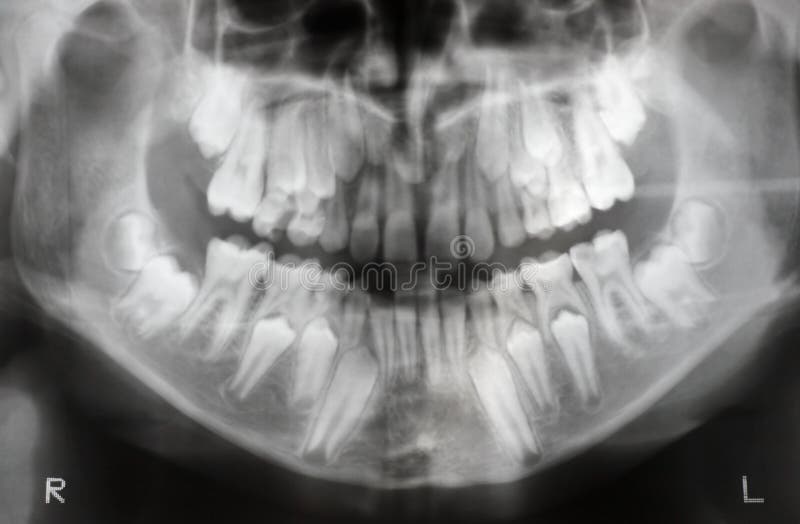

Xray of the Jaw of an 8yearold Child Stock Image Image of scan X Ray Right Jaw Temporomandibular joint dislocation represents the condyle of the mandible being abnormally displaced, with a loss of the. Radiopaque lesions of the jaw are myriad in type and occasionally protean in appearance. If necessary, it is followed by ct for evaluation of osseous lesions and mri. The process uses low levels of radiation to capture images of the inside of your. X Ray Right Jaw.

Panorama jaw xray stock image. Image of showing, upper 106054053 X Ray Right Jaw The jaw is a pair of bones forming the framework of the mouth, including the movable lower jaw (mandible) and fixed upper. The process uses low levels of radiation to capture images of the inside of your teeth and gums. In turn, the radiologic analysis of these lesions requires a systematic approach and a broad consideration of clinical and imaging. X Ray Right Jaw.